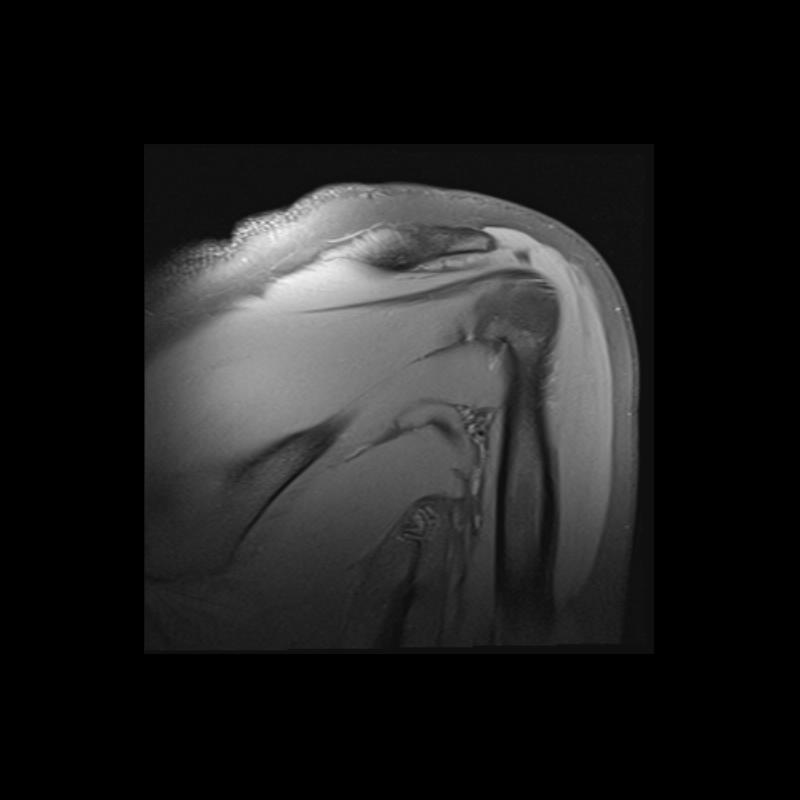

Shoulder MRI Anatomy